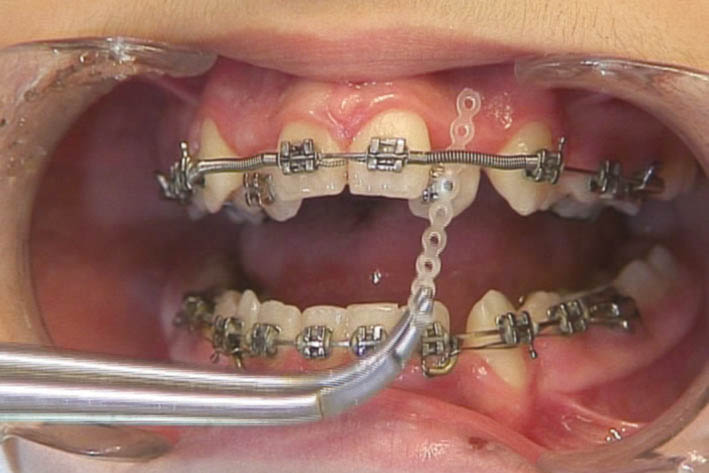

اگر استریپ قدامی کردهاید و فضا بین قدامیها ایجاد شده یا بین دندانهای قدامی Space وجود دارد میتوانید چینالاستیک را از براکت کانین تا کانین به مدت یک ماه بگذارید (شکل 156-1) اگر فضا بسته نشد هر ماه Chain Elastic را عوض میکنید تا سرانجام فضا بسته شود. بعد از بسته شدن فضا آن را برمیداریم و به صورت ضربدری از کانین تا کانین با سیم لیگاچور figure ∞ میزنیم تا فضا مجدداً باز نشود. بعد از اینکه فضا را بستیم اگر باز هم چینالاستیک بماند ایجاد کرادینگ میکند.

ضمناً حتماً باید کانینهای دو طرف با سیم لیگاچور بسته شود تا از چرخش آنها جلوگیری گردد. آرچوایر هم 0.020 استیل باشد تا جلوی tilt دیستالی یا مزیالی دندانها گرفته شود.

شکل 156-1: بستن فضاهای قدامی به کمک چین الاستیک